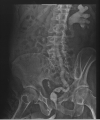

Results: Patient 1: A 58-year-old female had five episodes of acute left ureteral lithiasis in two years prior to left kidney tuberculosis. Patient 2: A 55-year-old male patient had a 1.2 cm proximal left ureteral stone and in the following six months, the diagnosis of tuberculosis was made in a nonfunctioning left kidney with ureteral thickening and stenosis. Patient 3: A 47-year-old male patient had a 1.2 cm stone in the proximal right ureter and developed urinary tuberculosis with a nonfunctioning right kidney and a contracted bladder.